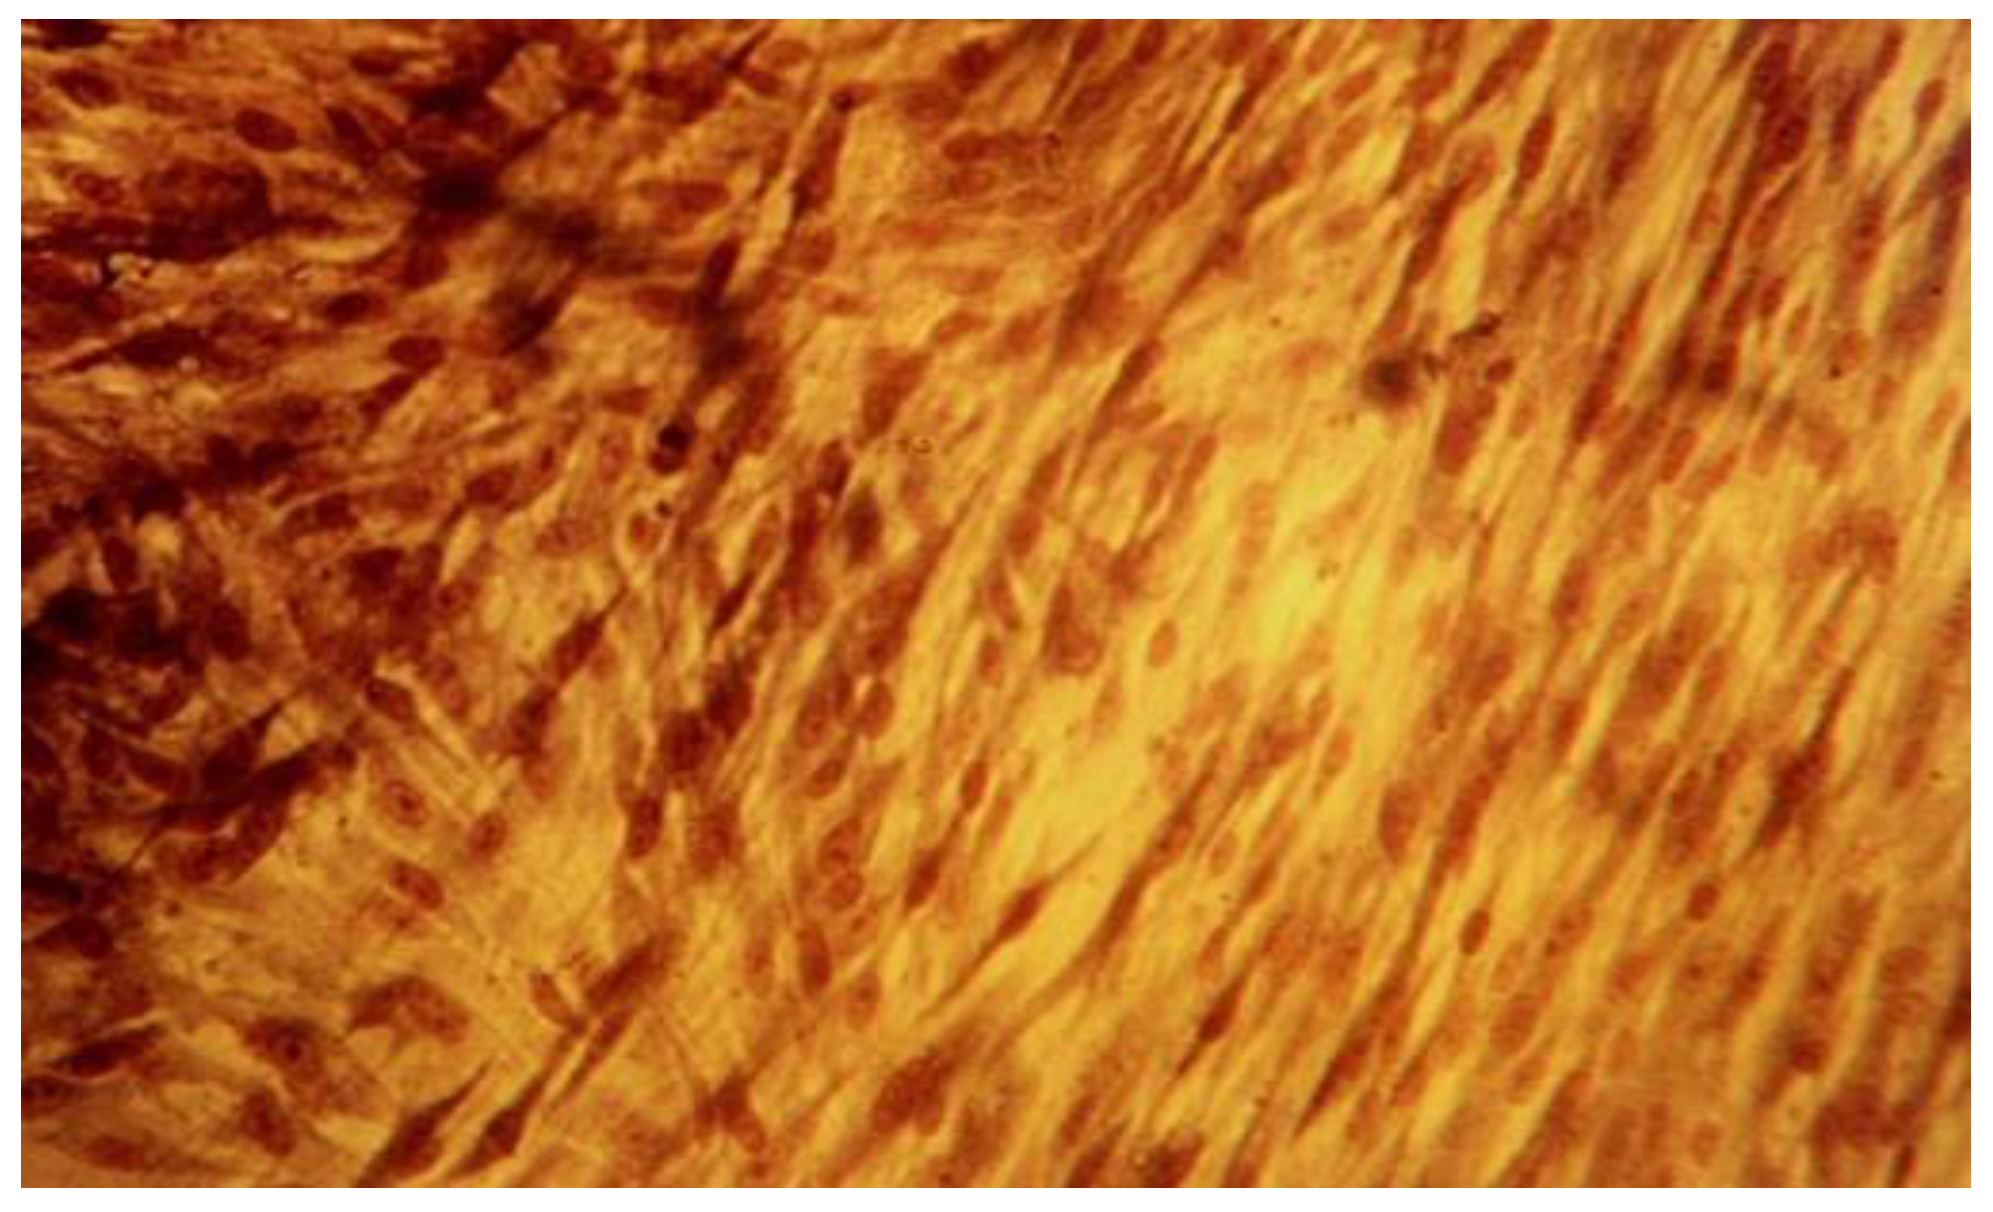

The qualitative expression of cytotoxicity was carried out microscopically and assessed by the cell cultures morphology analysis, reveals different degrees of cellular degeneration in contact with the investigated substances. We could observe different stages of membrane disintegration, nucleus changes and appearance of pathological pseudopodia.

Another specific aspect noted in this study is related to the appearance of the rounded cells detached form the monolayer, these being death or dying cells, as loss of adherence usually initiates apoptosis. The presence of dead cells is a result of pathological progression of cells alterations in contact with tested materials used in the study. They were floating in the suspension and their number increased during the entire experiment in the investigated lots as an indicator of the substances cytologic effect (Figure 5, Figure 6, Figure 7 and Figure 8).

The qualitative assessment of biological effect by microscopic examination of cellular appearance is consistent with values for the cellular dead rates and cellular density. Different changes in general cellular morphology, whose progressive evolution during the experiment, conducted to death cell, and detachment from substrate, have been observed. The observations indicate more obvious and visible aspects for MTA HP than BD and they have been presented descriptively. Nevertheless, the microscopic evaluations are in general more difficult to be precisely identified and must be always referred to the entire experiment and numerical data obtained. For MTA HP, more visible cell membrane integrity damages were observed, in association with a higher number of floating death cells. Loss of membrane integrity is a clear indicator for an unfavorable prognosis for cell survival [26]. For BD the morphological degenerative cell alterations were more discrete, and the presence of round detached cells less important. The rounded aspect is related to first sign of cellular injury, swelling, later followed by different nuclei and nucleoli alterations. No clear-cut delimitation between the healthy and affected cells were observed.

Figure 6. Fibroblasts cell line L929 at 96-hour mark, MTA Repair HP (Angelus, Brazil) lot, 40x magnification. Detached cells from monolayer, in suspension.